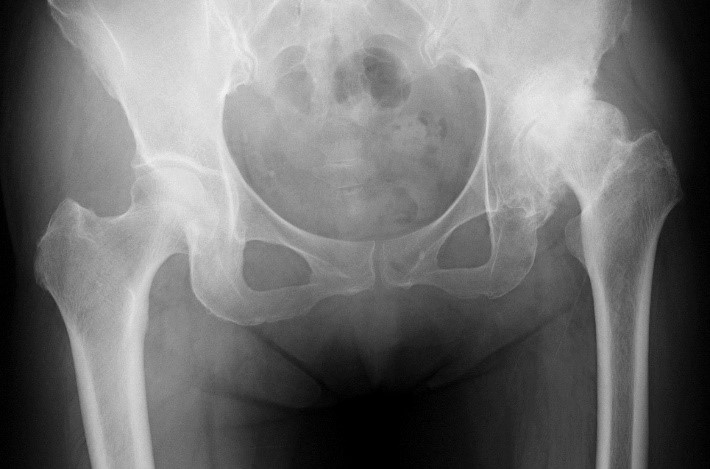

健側 患側

股関節の軟骨の変性・摩耗により関節破壊が生じ、それに反応性の骨増殖(変形)を特徴とする疾患です。進行すると靴下の着脱や爪切りが難しくなり、長時間の歩行が辛くなり、左右の脚長差が生じ歩容も悪くなります。股関節をかばうせいで腰や膝が痛くなることもあります。ひどくなると安静時痛・夜間痛も生じます。

図1 寛骨臼形成不全症

変形性股関節症(軟骨損傷)の発生機序は2種類に大別されます。日本で最も多いのは、寛骨臼形成不全症の不安定な股関節が原因で生じるタイプです(図1)。女性に多く認めます。